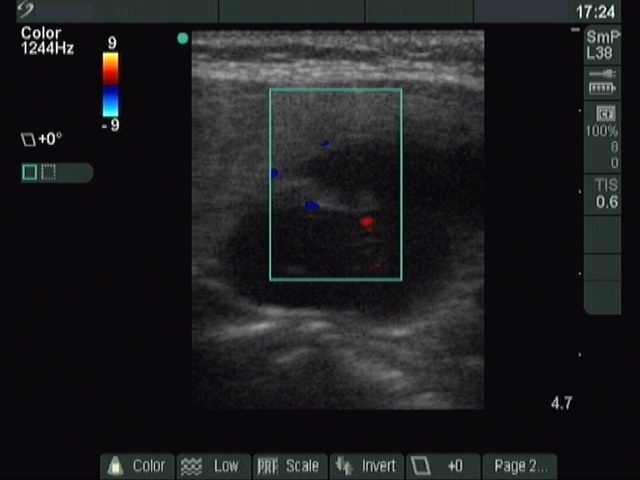

Clinical presentation: a 40-year-old woman was sent for ethanol sclerotherapy. Her thyroid cyst was evacuated three times but after each occasion the cyst got refilled within a week. FNAC resulted in a benign cystic lesion.

First row: before the first session of sclerotherapy. There was a cystic nodule in the left lobe with the dimensions of 32x27x42 mm (width x depth x length). 5 sessions of ethanol sclerotherapy was administered.